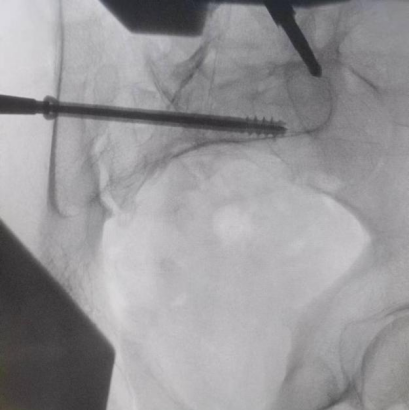

據(jù)了解,患者37歲,為高墜傷患者,入院合并顱腦挫傷、盆腔臟器出血、骨盆骨折多發(fā)傷患者。為最大限度降低手術(shù)風(fēng)險(xiǎn),同時(shí)給予患者滿意的手術(shù)療效,術(shù)前綜合評(píng)估患者病情,擬定行“天璣機(jī)器人”輔助定位下骨盆骨折微創(chuàng)手術(shù)。2月13日10時(shí),手術(shù)正式開始。拉薩市人民醫(yī)院采集患者術(shù)中二維影像,通過骨科手術(shù)機(jī)器人擬定螺釘打入位置方向后,吳宏華主任完成手術(shù)設(shè)計(jì),成功為該患者置入了一顆高難度骶髂螺釘,出血5ml,切口1cm。術(shù)后圖像顯示,螺釘位置及方向完全符合手術(shù)規(guī)劃,沒有一絲偏差,手術(shù)最終獲得圓滿成功。

圖為透視下見置入的骶髂螺釘,位置、長(zhǎng)度精準(zhǔn),無(wú)絲毫偏差